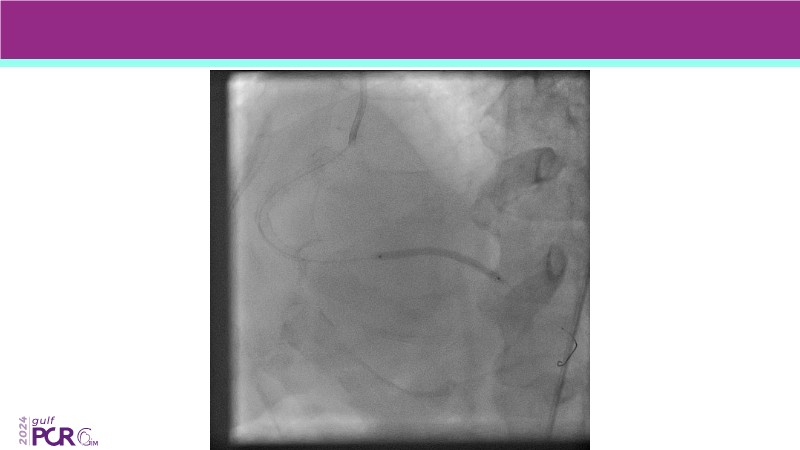

- To discover your next gen complex PCI toolkit with thin strut platforms and dedicated stenting solutions for managing side branch and long diffused lesions